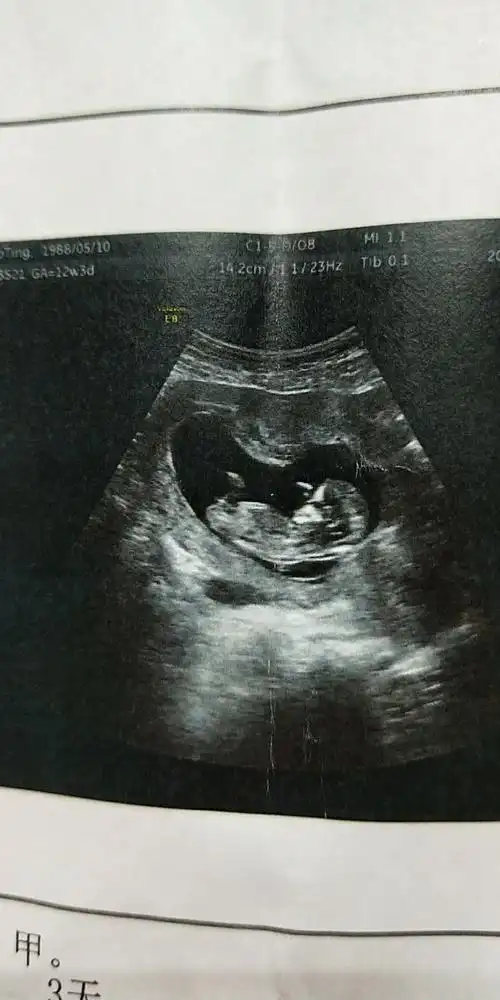

孩子12周的b超图,同事说孕瓤是茄子形状,多是男孩,大伙怎么看?